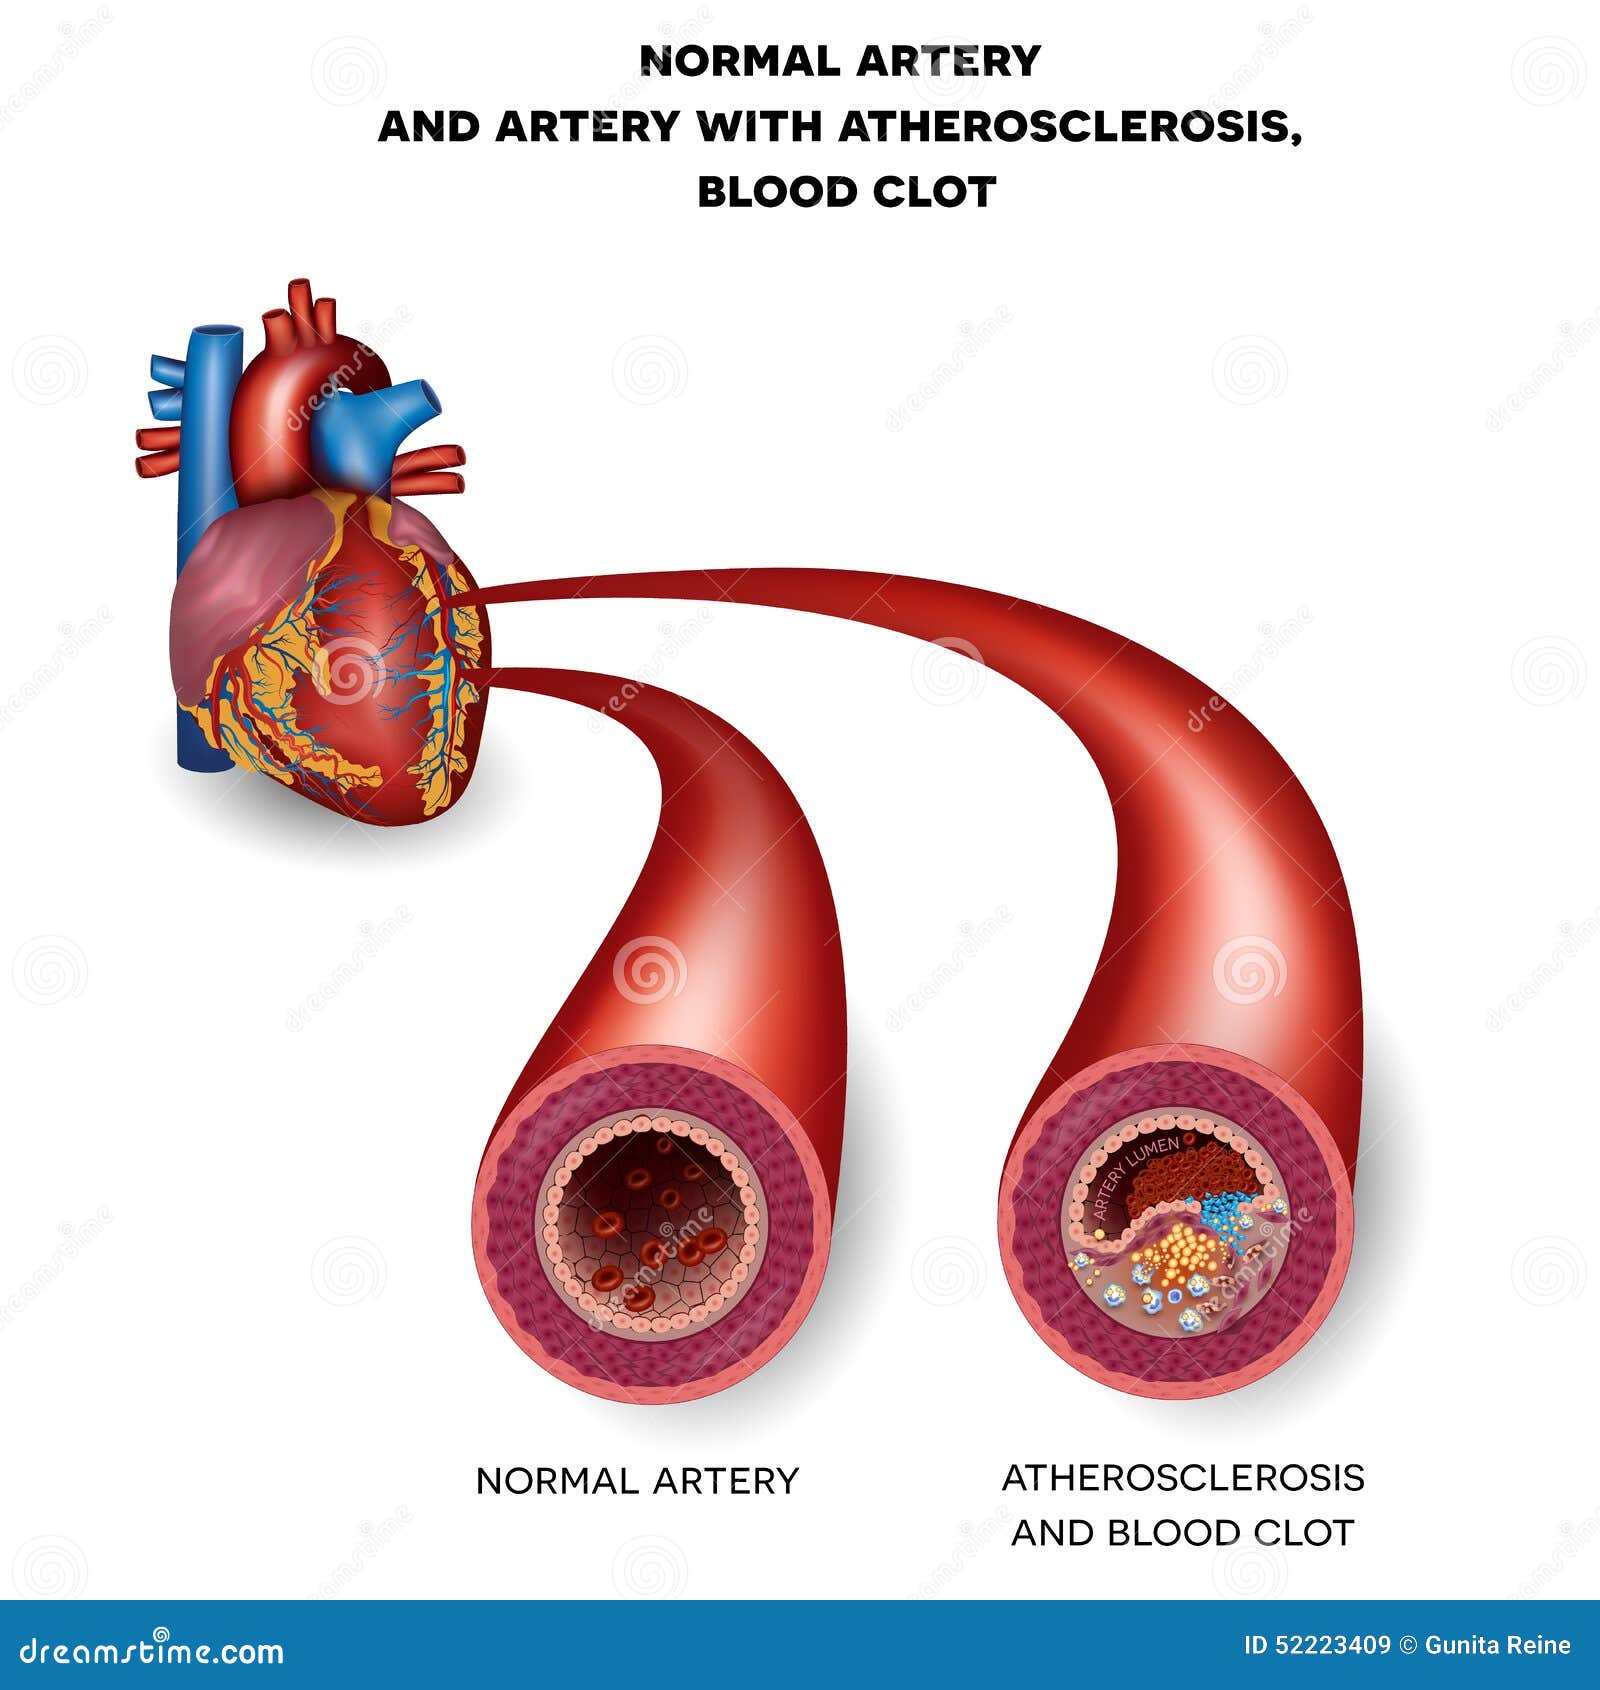

Normal Artery And Unhealthy Artery Stock Vector – Image: 52223409

Heart Attack

Coronary Artery Disease: Symptoms, Causes & Treatment